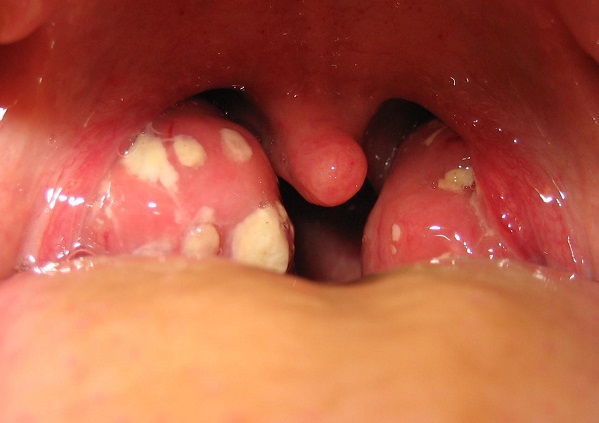

Активизация стафилококка в горле приводит к развитию ряда заболеваний:

- Тонзиллита (воспаления небных миндалин – в народе гланд).

- Фарингита (воспаления глотки).

- Аденоидита (воспаления глоточного лимфоидного образования – глоточной миндалины).

Симптомами этих недугов могут быть:

- Першение и боль в горле.

- Увеличение гланд.

- Покраснение задней стенки горла.

- Гипертермия (температура может быть повышена незначительно).

Стафилококк в горле — это инфекция, которая может вызывать различные симптомы, включая боль в горле, затрудненное глотание и общее недомогание. Люди часто отмечают появление гнойных пробок и неприятного запаха изо рта. Визуально это может проявляться в виде покраснения и отека слизистой оболочки. При наличии таких симптомов важно обратиться к врачу для диагностики и назначения лечения. В большинстве случаев терапия включает антибиотики, которые помогают справиться с инфекцией. Также рекомендуется полоскание горла антисептическими растворами и использование противовоспалительных средств. Профилактика включает соблюдение гигиенических норм и укрепление иммунной системы.